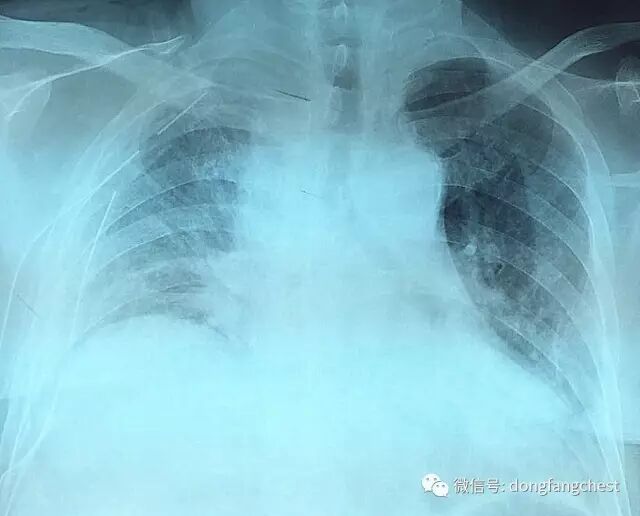

年近70岁的李老爷子,反复咳嗽了一个月不见好,于2016年12月在东方总院拍CT,检查发现”右肺上叶恶性肿瘤“。

由于肿瘤体积较大,且与肺动脉、上腔静脉关系紧密,手术实施起来较为困难,经过东方总院多学科讨论会诊,决定先于呼吸内科进行了2个疗程新辅助化疗。

手术后胸片肺复张良好,可以自主生活,状态平稳,待明天拆线后,即可出院。